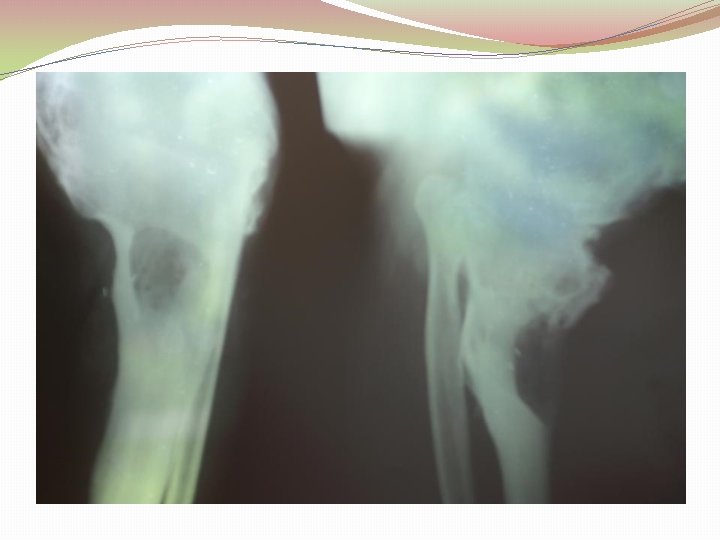

Diagnostika �Klīnika �Laboratoriskie izmeklējumi (asins aina, EGĀ, CRP, uzsējums no brūces) �Kaula palpācija (Probing to bone test) �Rtg, MRI, DT, kaulu scintigrāfija, USS �Kaula biopsija (zelta standarts)

Diagnostika �Rentgena izmeklējumi (x-ray) �Datortomogrāfija �Ultrasonogrāfija �Radionuklīdā skenēšana (Technetium-99 m; Gallium 67 ) �Magnētiskā rezonanse (MRI)